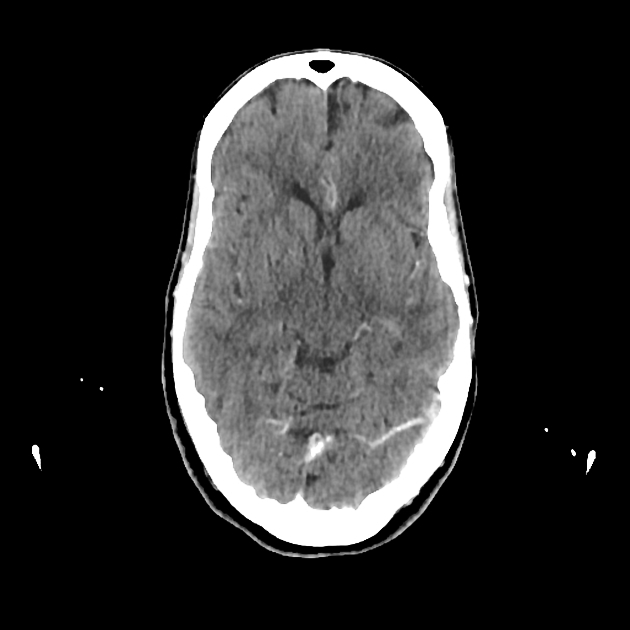

Epidermoid: purely neuroectoder, fluid-like content, T2 complex bright, T1 hypointense, homogenenous/poor enhancement of capsule, and restricted diffusion. 20-40 yearsof age behind ears. Dermoid: Neuroectoderm+glands, lipidic-like content, T2 bright, T1 hyperintense, calcification of capsule, enhancement of capsule. Earlier presentation and midline. Nasal dermoid cysts may be associated with a sinus tract that extends for variable distances in the prenasal space to the foramen cecum. Nasal dermoid and epidermoid cysts are typically surgically resected due to the potential for an intracranial connection and the risk of CNS infection, as well as for cosmetic reasons IMAGE 1 Epidermoid IMAGE 2: Nasal dermoid